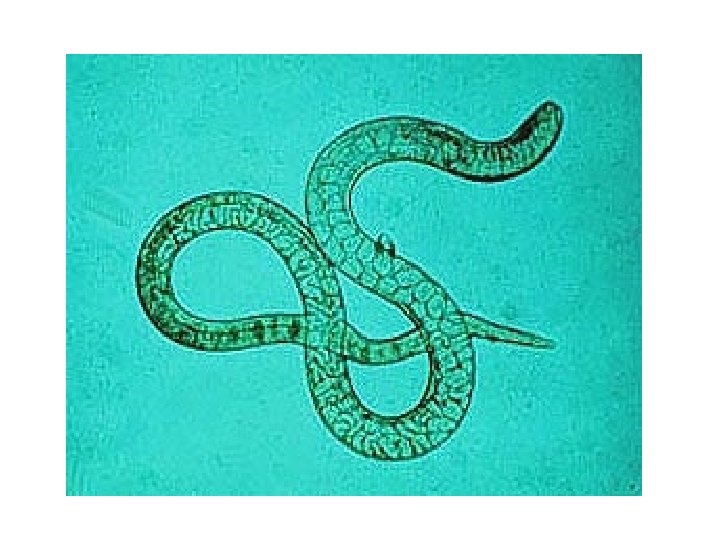

Male Female Free living adult of strongyloides stercoralis